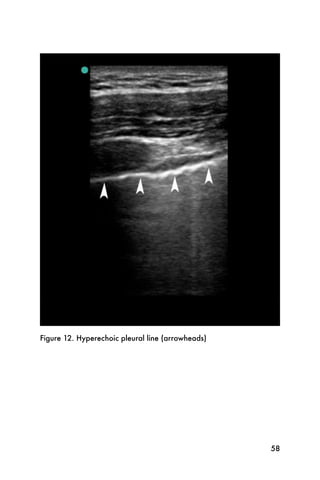

video, a still image of the pleural line is shown in Figure

12. In patients with pleural adhesions from previous

pathology, such as obstructive lung disease from long-

standing tobacco use or history of pleurisy, this finding

may not be detected, even in the absence of a

pneumothorax.

Figure 12. Hyperechoic pleural line (arrowheads)